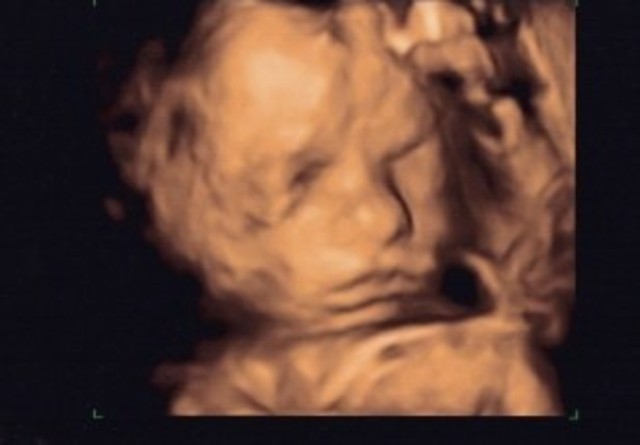

• Ecografía

Ecografía

Aquí estas dentro de la tripa de mamá, cuando estaba de 6 meses.